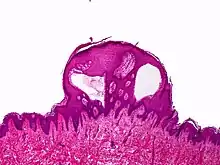

Lymphangioma circumscriptum; only stratum papillare is affected.

A biopsy of the affected skin and histological examination under a microscope are necessary to confirm the diagnosis of lymphangioma circumscriptum.